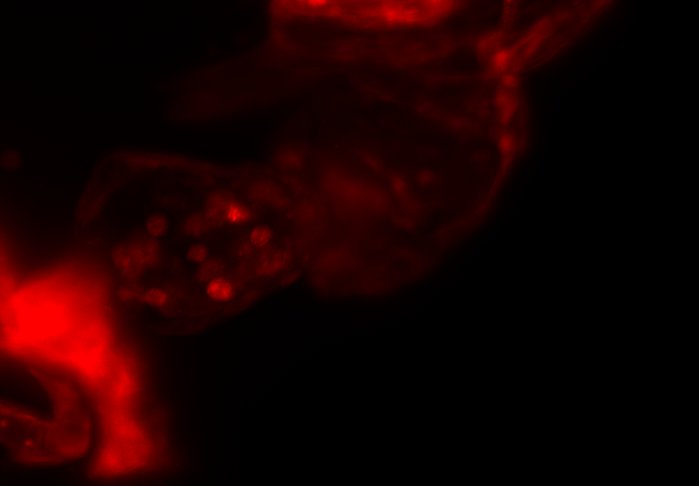

The combination of prospective optical gating for real-time phase matching and prospective optical gating for long-term phase locking allow us to capture in phase images over extended periods of times. Figure 4 demonstrates this phase locking over 18+ hours across a key developmental phase - heart looping.